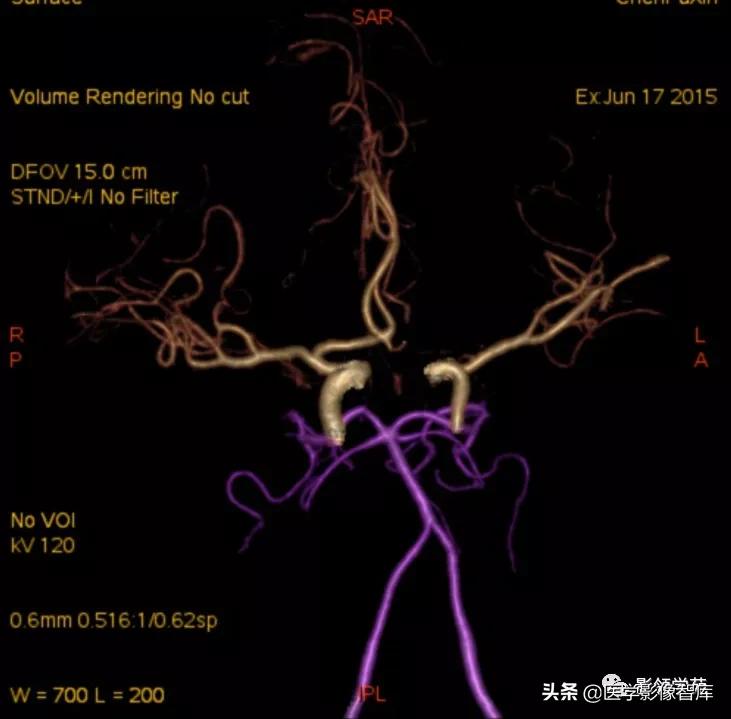

- DSA-金标准、最可靠,但有创,且不能显示完全血栓化的动脉瘤,而CT、MRI则可显示。(CTA、MRA可诊断,尤其是MSCTA具有较高的敏感性和特异性。)

头颅CTA:基底动脉起始部血管局部瘤样突起(宽基底),无占位效应。

动脉瘤:光滑,流空信号,CTA、MRA